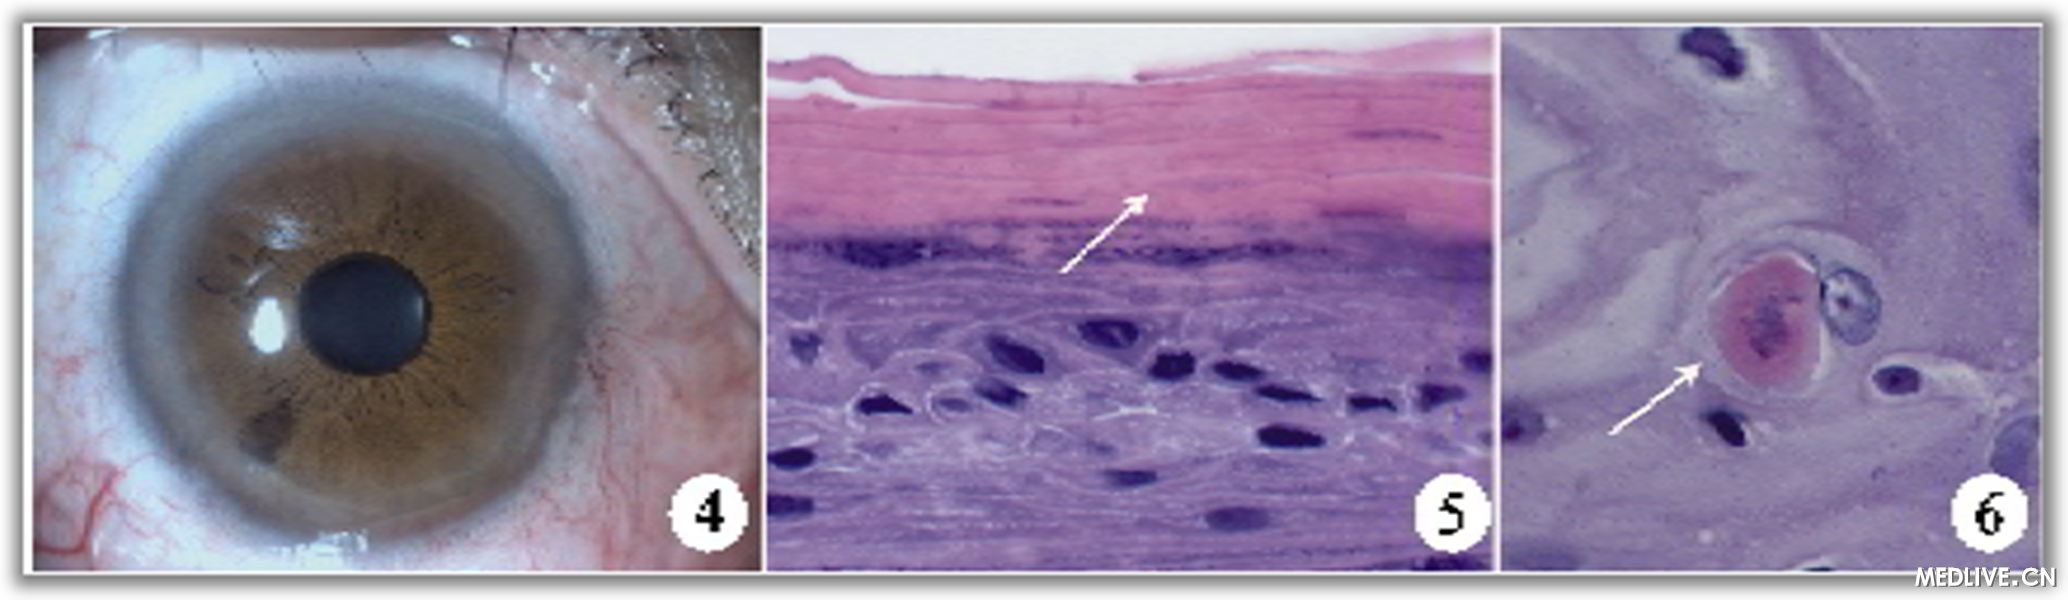

完善术前检査后,在爱尔卡因表面麻醉下,行右眼角膜上皮性肿物切除术,术中见上皮性肿物与角膜前弹力层无明显粘连,易分离,病灶基底光滑,给予彻底切除后,治疗性角膜接触镜覆盖创面,切除组织送病理,妥布霉素眼药水每日三次点眼,预防感染。一周后复诊去除接触镜,角膜创面生长良好(图4)。视力:右眼0.8。角膜病灶病理检査:右眼角膜上皮细胞增生、增厚,表面有角化物覆盖,部分区域上皮细胞增生活跃,呈异型性,基底膜完整(图5,6)。最后诊断:右眼角膜上皮不典型增生。半年后随诊未见复发。

图4角膜病灶切除术后,角膜透明,无云翳形成,视力1.0

图5右眼角膜上皮细胞增生,表面覆盖较厚的角化物(白箭)(HE×400)

图6右眼角膜上皮细胞增生活跃,呈异型性(白箭)(HE×1000)